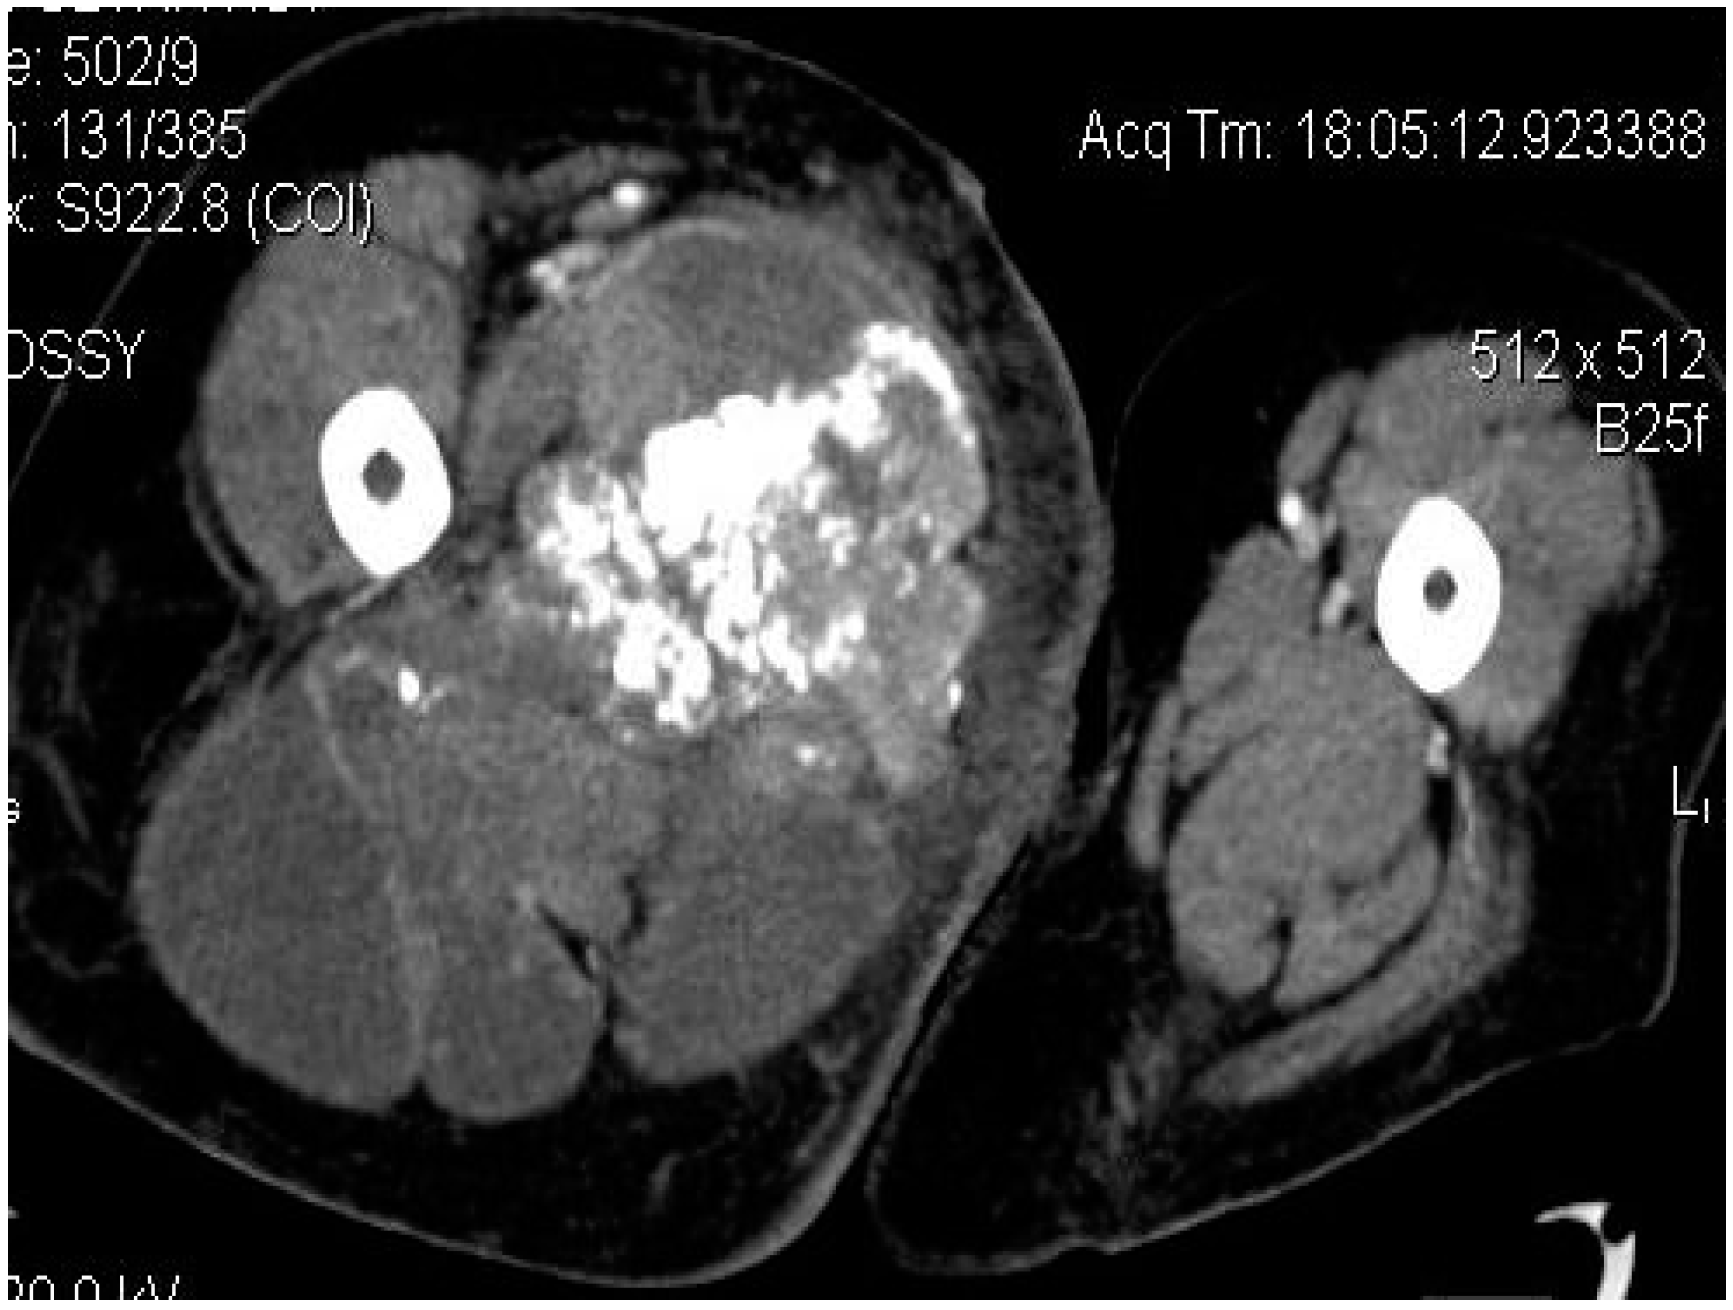

Computed tomography (CT) is usually performed either if the MRI is contraindicated (e.g., due to the presence of orthopedic implants), is unavailable or if the radiologists need additional information regarding the local bone involvement or better visualization of the intratumoral calcifications (Figure 4, Figure 5 and Figure 6).

Figure 4.

Axial CT-scan: evident enlargement of the right thigh; heterogeneous soft-tissue mass with calcifications, adjacent fat infiltration and skin thickening—synovial sarcoma, M, 26 YO patient.